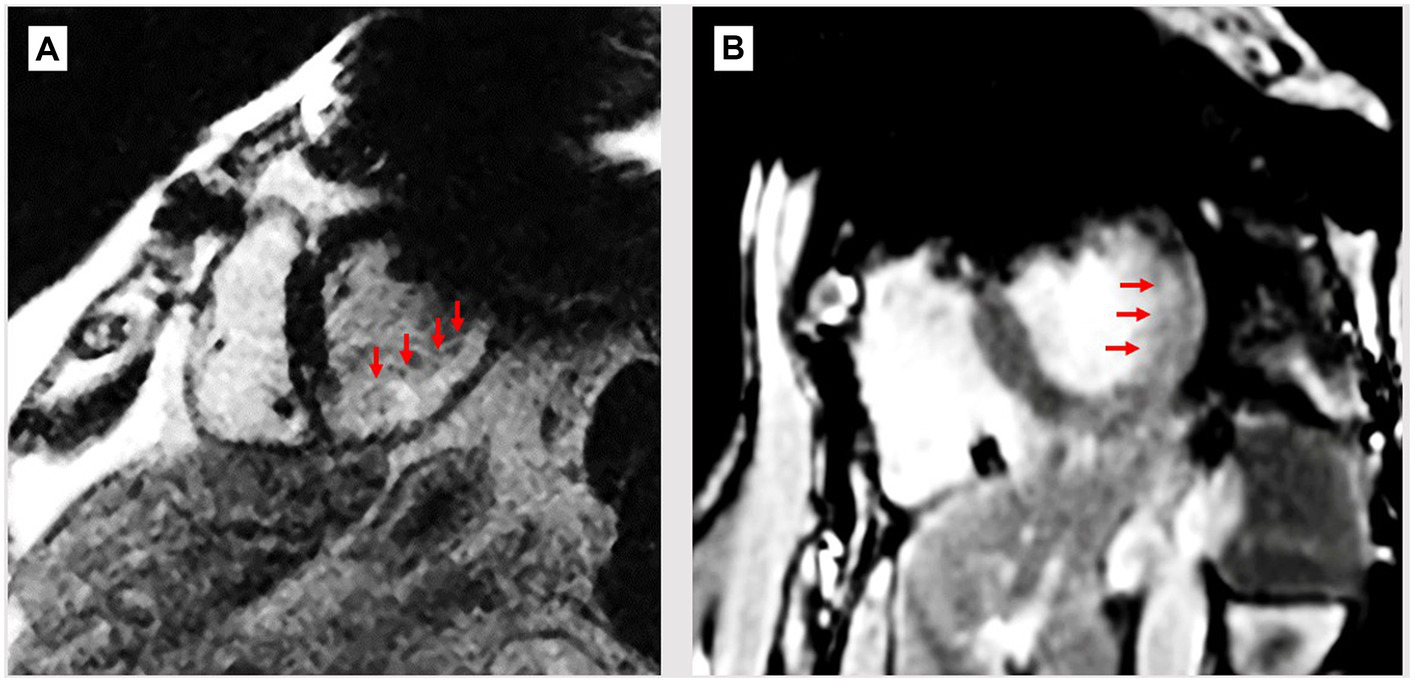

Figure 2

Breath-held wideband LGE scans of patients with ICDs and myocardial infarcts. (A) ICD-generated void still covers upper left of LV wall, possibly hiding extension of scar (bright region, red arrows). (B) Patient with thin mid-wall scar (arrows) which may extend into the void region, which remains despite WB sequence.